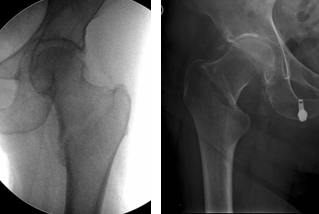

La falla en la osteosíntesis (TDC) ocurrió en 7 caderas (14,9%) dentro los 6 meses posteriores a la cirugía. Se identificaron las siguientes descripciones en las HCE; ruptura del implante por caída del paciente, resuelto con una nueva osteosíntesis (cambio de una placa de 4 orificios por una de 10). Un caso de necrosis ósea avascular de la cabeza femoral, revisado con una artroplastía con prótesis tipo Monoblock. Se identificó “cut-out” (protrusión del tornillo fuera de la cabeza femoral, en su terminología del inglés) en 3 pacientes (por mala reducción y fijación de la fractura, sin alcanzar la distancia punta-apex correcta, lo cual condujo a la protrusión del tornillo fuera del cuello y cabeza femoral), dos reintervenidos con prótesis tipo Monoblock y uno con un RPC. En otros 2 pacientes se decidió tratamiento conservador por condiciones clínicas inherentes a los mismos.

El TDC ha sido el implante más utilizado en nuestra serie. Su abordaje es simple y pequeño; no altera el canal medular, lo que conduce a una pérdida de sangre mínima; y, si es necesario, la conversión a un reemplazo articular, es un procedimiento más simple que el del CCM (16). Sin embargo, existen tasas de falla por factores como la inestabilidad propia de la fractura, reducciones inadecuadas, mala colocación del cañón y baja densidad ósea del paciente. Por lo tanto, para estas fracturas osteoporóticas, su uso debe reservarse para pacientes con trocánter menor intacto y pared lateral conservada, como pueden ser las FBC. El tornillo de compresión, en ocasiones rota la cabeza femoral durante su inserción, un factor que puede aumentar la incidencia de necrosis aséptica y falta de unión. Para prevenir esta complicación, durante la cirugía, se debería insertar una segunda clavija antirotatoria superior a la guía. Otro punto en contra al implante es que algunos autores consideran que la función de la articulación de la cadera puede verse comprometida (17) debido al acortamiento del cuello femoral con discrepancia de miembros, como resultado de una compresión sustancial de la fractura.

Pascarella y cols. (22) examinaron 321 fracturas intertrocantéricas, incluidas FBC, tratadas con CCM, encontrando que las complicaciones intraoperatorias más comunes son la reducción incorrecta de la fractura o la colocación incorrecta del tornillo de posición.

Para evitar esto, se recomienda que los pacientes se coloquen adecuadamente en una mesa de tracción, dando 10 grados de rotación interna a la extremidad para lograr una adecuada reducción antes de comenzar la cirugía. El canal femoral debe ser escariado 2 mm más grande que el diámetro del clavo distal para evitar fracturas intraoperatorias. La mala colocación del tornillo cefálico conduce a la complicación postoperatoria más común, la protrusión del tornillo fuera de la cabeza femoral, conocida como “cut-out” en su terminología del inglés (23). La posición ideal de éste es en la porción inferior del cuello femoral en el plano frontal y en la línea media en el perfil. Otra recomendación, es un punto de entrada sobre la punta del trocánter mayor, dado que si es lateral puede provocar estrés en la corteza medial cuando se inserta el clavo, lo que conduce a fracturas. También otros autores sugieren, para mejorar los resultados, el uso de tracción femoral distal o tibial para ayudar a reducir y minimizar la tensión de los tejidos blandos preoperatoriamente (22).